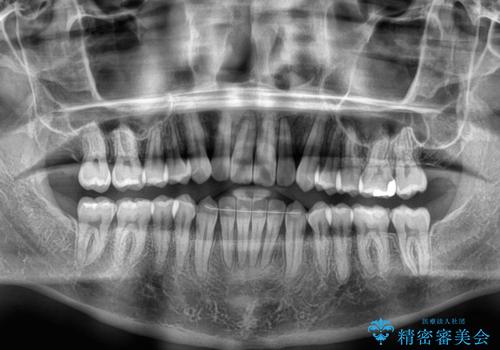

オープンバイトをインビザラインで矯正治療

- 前歯の開咬を気にして来院された患者様です。

開咬の治療は、前歯を閉じるように動かすとともに、上下臼歯を圧下(骨内にめり込ませる)させることで進めて行きます。

インビザラインは臼歯の圧下を効果的に行えるため、インビザラインを用いて矯正治療を行うこととしました。

オープンバイトは舌の突出癖により誘発され、治療後も突出癖が残っている容易に後戻りしてしまいます。

治療期間を短縮するためにも、舌突出癖の改善が極めて重要となります。

特にインビザラインではIPRという歯と歯の間を削る処置を多用するため、後戻りによりスペースが生じやすくなるため、治療初期段階での舌のトレーニングが必須となります。